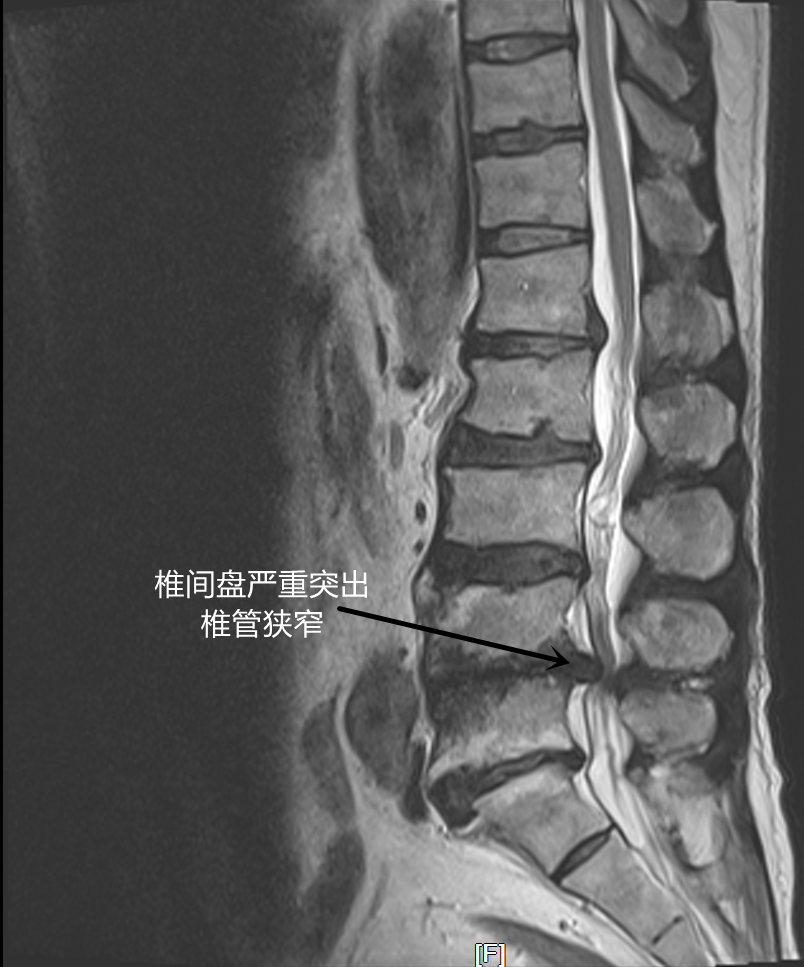

57 岁的患者施某,因大小便无法控制、双腿麻木无力、行走困难,辗转多家医院都没得到明确的诊断,近日,坐着轮椅来到我院骨科就诊。李清主任接诊后,详细了解患者病史、查体、做了相应的检查,得出结论——患者是多节段腰椎管狭窄合并马尾神经损伤。

从临床影像学表现看,患者马尾神经损伤已经相当严重,濒临瘫痪,李清主任立即把患者收入院。入院检查发现患者感染指标异常,内分泌科、影像科、感染科专家会诊,寻找感染原因,排除手术风险后,于第三天为患者进行手术。